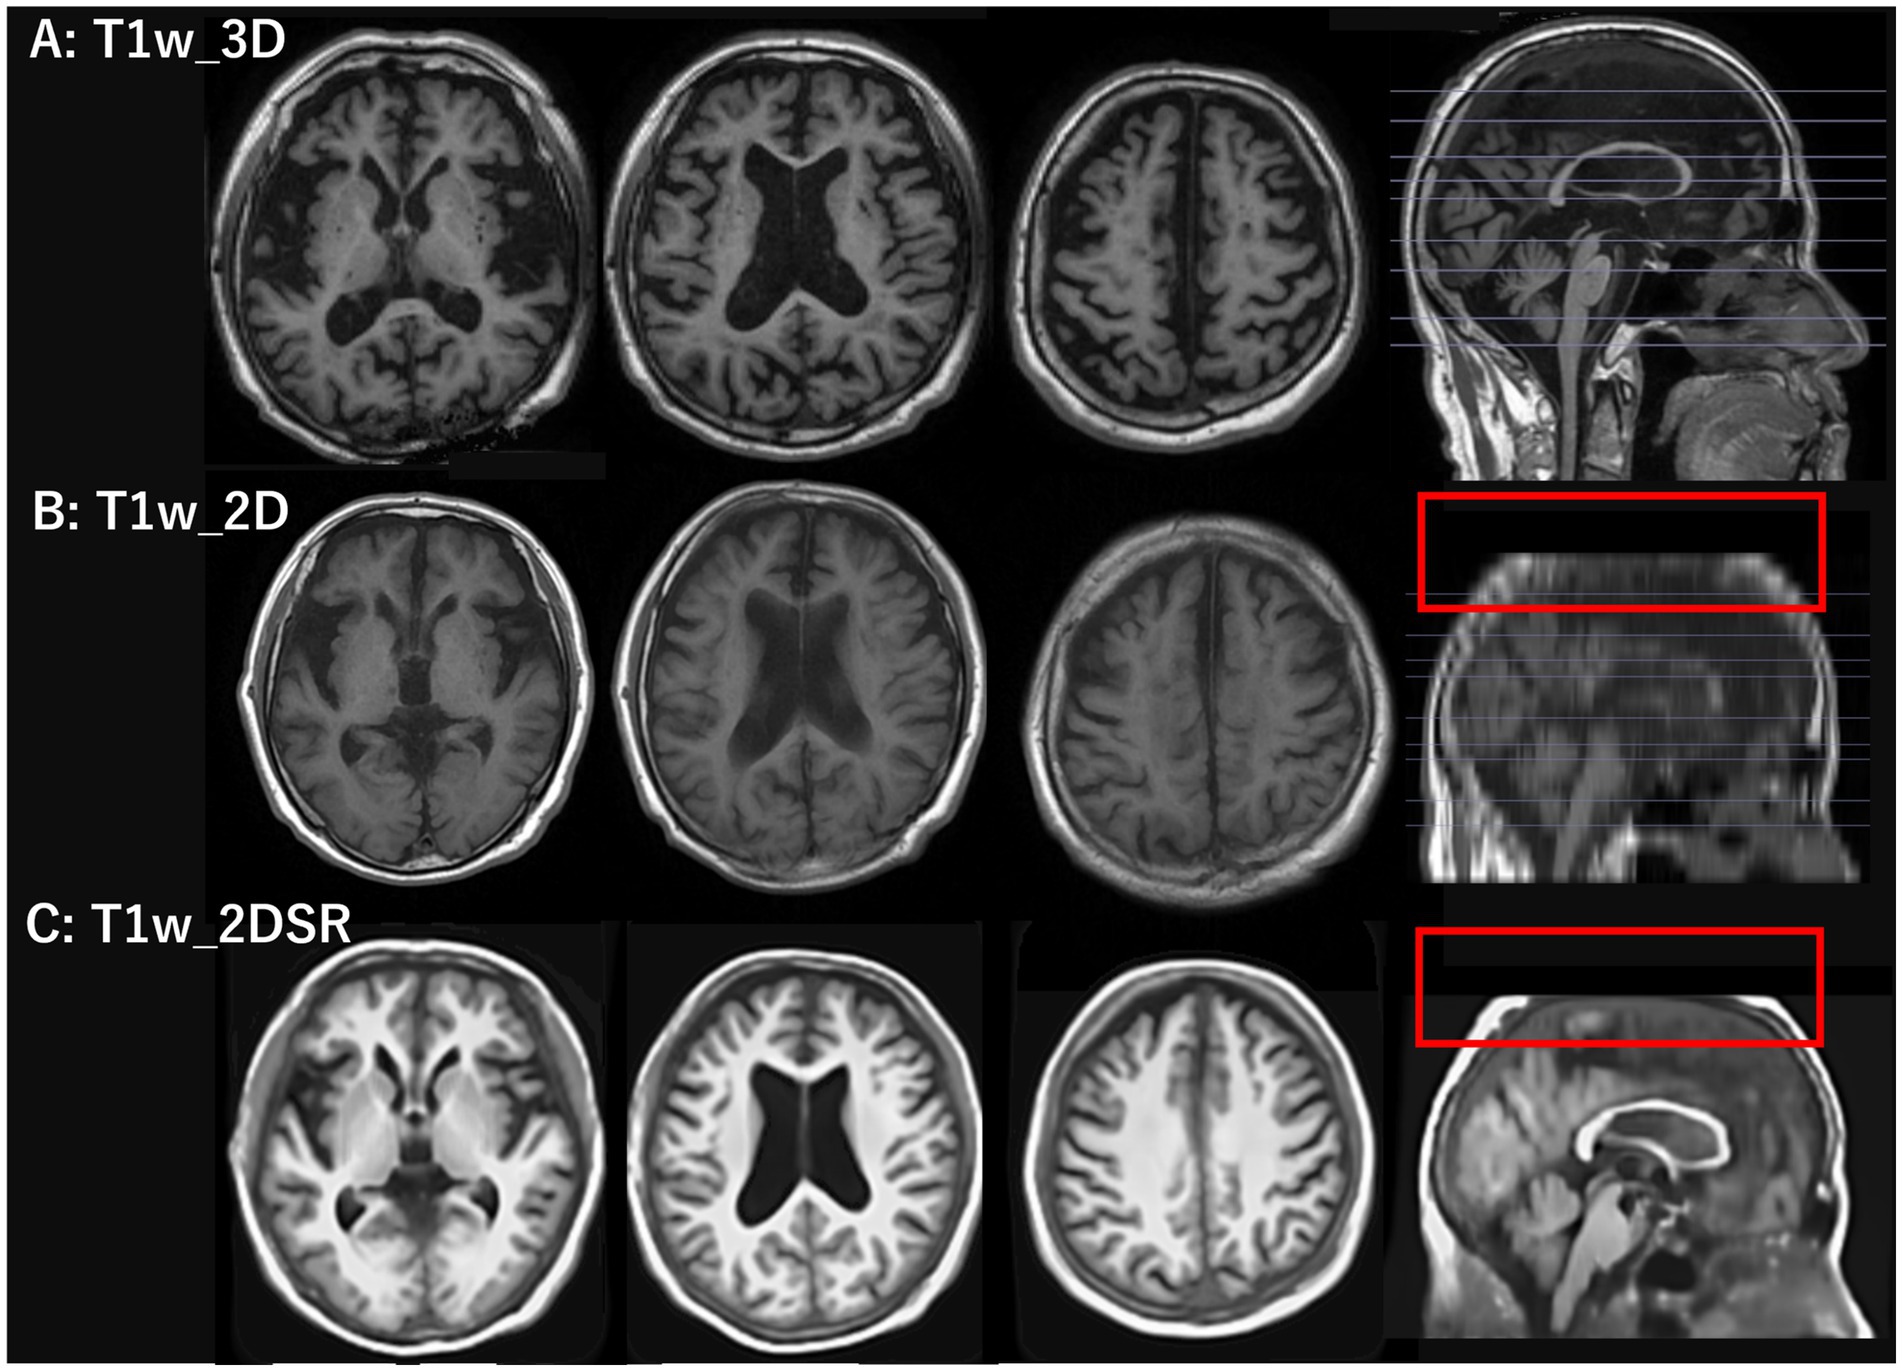

T1w_2D images were converted from DICOM to NIfTI format using MRIcroGL (20). The 3D volume data (T1w_2DSR) were generated using FreeSurfer’s SynthSR from T1w_2D modified to NIfTI file format (13–15). SynthSR was used with default settings, except that 4 CPU threads were specified. The 3D volume was output as a 1.0 mm MPRAGE-like image with standard contrast, bias magnetic field correction, and inpainting of white matter lesions. The average time for T1w_2DSR generation was 77 s. The generated T1w_2DSR was in NIfTI format. Since VSRAD required DICOM in the sagittal orientation, the image was reoriented from axial to sagittal and converted to DICOM format using 3D Slicer (Figure 1) (21). All processing was performed under Windows Subsystem for Linux 2 (WSL2) using a laptop computer ThinkPad X1 Extreme (Lenovo Japan LLC, Tokyo, Japan) with the following specifications: Intel Core i7-8750H CPU (up to 4.10 GHz), 32 GB RAM (Intel Corp., California, USA), and NVIDIA GeForce GTX 1050 Ti with Max-Q Design (Nvidia Corp., California, USA).

Figure 1. T1-weighted images used in the standard and proposed methods. The top row shows 3D T1-weighted images acquired using spoiled gradient recalled acquisition in steady state (SPGR) sequence with the standard method. The middle row shows 2D T1-weighted images acquired using periodically rotated overlapping parallel lines (PROPELLER), which are commonly used in clinical settings. The bottom row shows 3D volume data generated from 2D T1-weighted images using FreeSurfer’s SynthSR tool. The red rectangles in the middle and bottom rows indicate that the parietal region was not included in the original scan and therefore could not be generated.